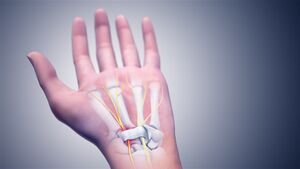

In the human body, the carpal tunnel or carpal canal is the passageway on the palmar side of the wrist that connects the forearm to the hand.[1]

The tunnel is bounded by the bones of the wrist and flexor retinaculum from connective tissue. Normally several tendons from the flexor group of forearm muscles and the median nerve pass through it. There are described cases of variable median artery occurrence.

Structure

The carpal bones that make up the wrist form an arch which is convex on the dorsal side of the hand and concave on the palmar side. The groove on the palmar side, the sulcus carpi, is covered by the flexor retinaculum, a sheath of tough connective tissue, thus forming the carpal tunnel. On the side of the radius, the flexor retinaculum is attached to the scaphoid bone, more precisely its tubercle, as well as the ridge of trapezium. On the ulnar side, it is attached to the pisiform and hook of hamate.[4]